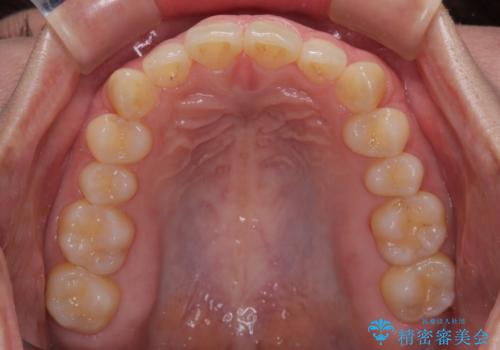

- 下顎前歯が完全に隠れてしまっていることを気にして来院された患者様です。

下顎の臼歯が手前に傾斜していることで咬み合わせが深くなってしまい、下顎前歯が見えないほどに上顎前歯が覆い被さっている状態でした。

下顎臼歯を起き上がらせるためにユーティリティーアーチを使用し、一気に深い咬み合わせを改善することができました。